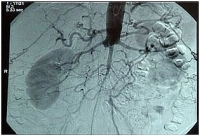

Oclusão aórtica alta com estenose subtotal da bifurcação ilíaca, oclusão da AIC direita e trombose na AIE esquerda (estágio clínico Fontaine bilateral IIb).

-> TASC II D, portanto recomendação para revascularização aberta

DSA intra-arterial pré-operatória